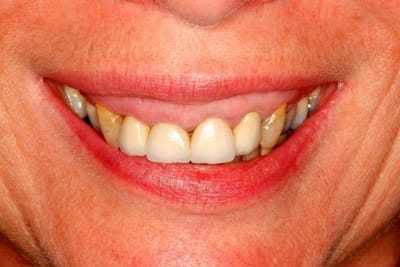

Suite :

Paro stable, furcation normale.

Patiente ne désire pas de chirurgie style Lefort (pour le gummy smile), ni d'ortho.

J'ai placé 2 implants (14 et 35)

Le bridge 34-X-36 était brisé et troué (pour une endo), et la patiente désirait des dents unitaire.

J'ai placé des provisoires de 13 à 23 suite à

l'élongation de 13 à 23 et apectomie 12.